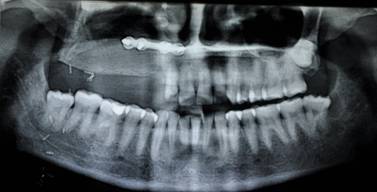

PRE OP OPG AND P A WATER'S VIEW SHOWS DISEASE